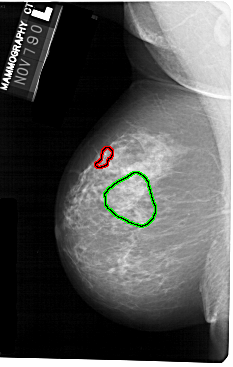

FILE: A_1251_1.LEFT_MLO.OVERLAY

TOTAL_ABNORMALITIES 1

ABNORMALITY 1

LESION_TYPE CALCIFICATION TYPE PLEOMORPHIC DISTRIBUTION LINEAR

ASSESSMENT 5

SUBTLETY 5

PATHOLOGY MALIGNANT

TOTAL_OUTLINES 1

BOUNDARY

ABNORMALITY 2

LESION_TYPE MASS SHAPE IRREGULAR MARGINS ILL_DEFINED

ASSESSMENT 4

SUBTLETY 3